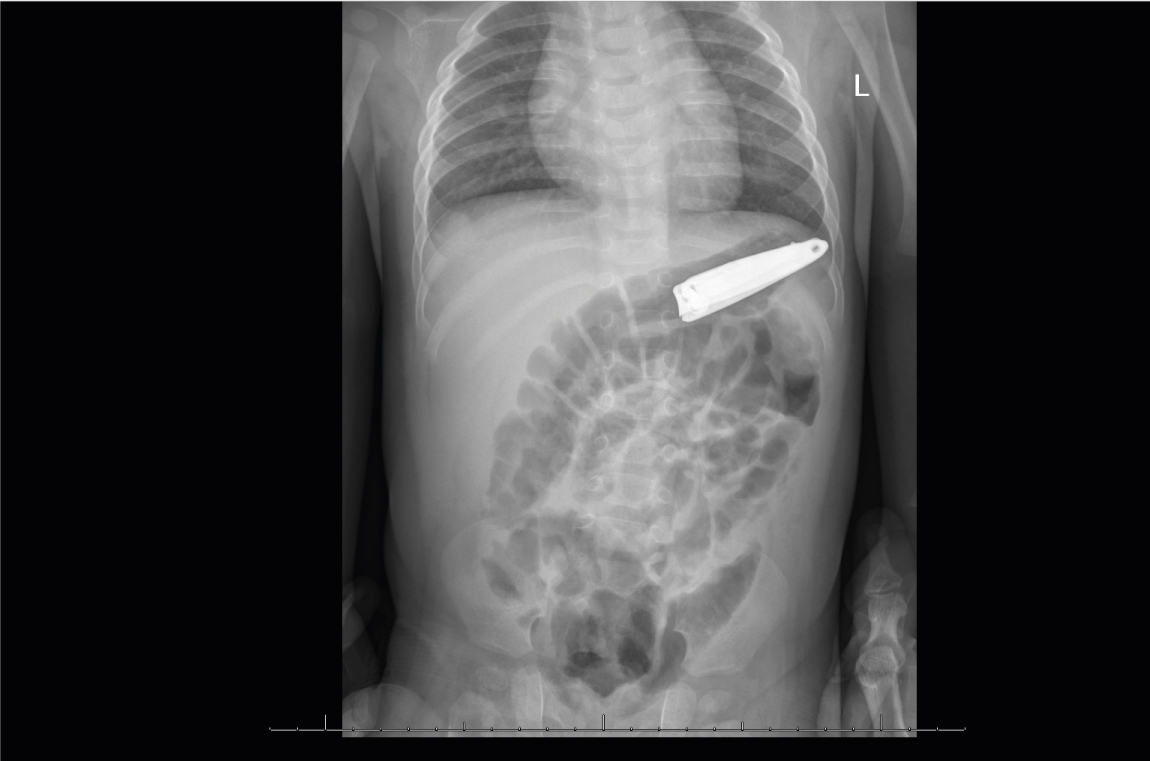

أحضر طفل يبلغ من العمر 7 شهور الى قسم الأطفال بمستشفى المواساة بالدمام بعد ملاحظة أمه لبلعه مقص الأظافر حيث طلبت الأستشارة الطبية في المستشفيات الأخرى و لعدم توفر الخدمة هناك تم تحويله الى مستشفى المواساة بالدمام وبعد التصوير الشعاعي تبين وجود الجسم الغريب داخل المعدة و تم استشارة الدكتور ايهاب زريقات استشاري الجهاز الهضمي للأطفال حيث أجريت العملية وتم استخراج الجسم الغريب بالمنظار دون اللجوء الى الجراحة التي كانت الخيار الثاني و تعتبر هذه الحالة من الحالات النادرة في مثل هذا العمر.